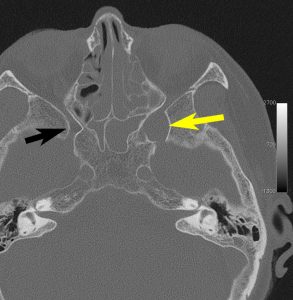

三叉神経鞘腫は,頭蓋底の孔(上眼窩裂,正円孔,卵円孔)から眼窩内や頭蓋底,鼻咽腔に伸びることがあります。CTで頭蓋底骨の孔の拡大があることで診断がつきます。bone erosionといって徐々に大きくなる腫瘍の特徴的な所見です。

左上顎癌と間違えそうなMRI画像です。CTでは左の正円孔(黄色の矢印)が辺縁が滑らかに拡大 erosion しているので三叉神経第2枝(上顎神経)の神経鞘腫の診断がつきます。